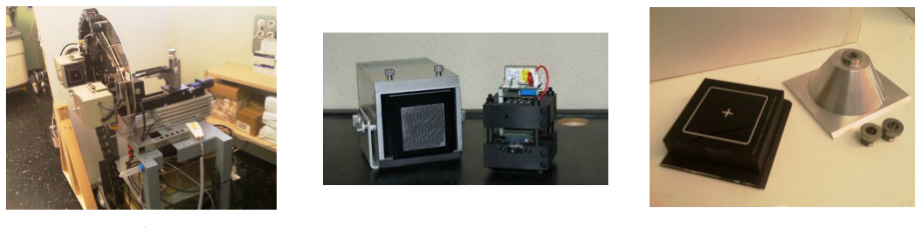

This work reports on the development and evaluation of the PET component of a PET/CT system for small-animal in-vivo imaging. The PET and CT subsystems are assembled in a rotary gantry in such a way that the center of rotation for both imaging modalities is mechanically aligned. The PET scanner configuration is based on 2 detector modules, each of which consist of 2 flat-panel type PS-PMTs (Hamamatsu, H8500) and 2 (30 × 30 elements) LYSO arrays.

|

Este trabajo describe el proceso de desarrollo y la evaluación inicial de un nuevo sistema tomográfico PET/CT de alta resolución, enfocado a la realización de estudios preclínicos “in-vivo” con animales de laboratorio. En el diseño implementado, los centros geométricos de cada modalidad de imagen están alineados mecánicamente permitiendo la obtención de conjuntos de datos con información anatómica y funcional que se registran y fusionan de forma automática.